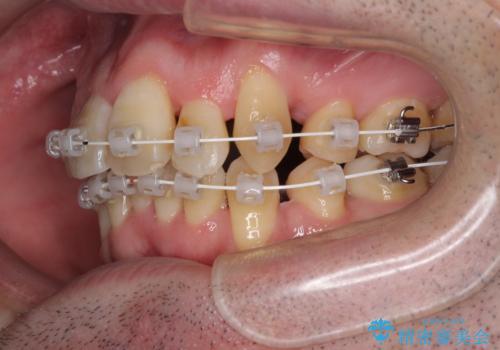

ものが挟まる 著しい叢生を解消 ワイヤー装置による抜歯矯正

- 審美装置

- 前歯のデコボコを気にして来院された患者様です。

叢生の解消とともに、前方に張り出した上顎前歯を引っ込めることを目的とし、上下左右の第一小臼歯4歯を抜歯をしてワイヤー矯正により治療することとしました。

治療開始直後は、あっという間に歯列が整い、すぐに終わるのではないかと思われましたが、治療の後半にブラックトライアングル解消のための処置を行ったため、当初予定していた2年半ほどの期間を要することとなりました。